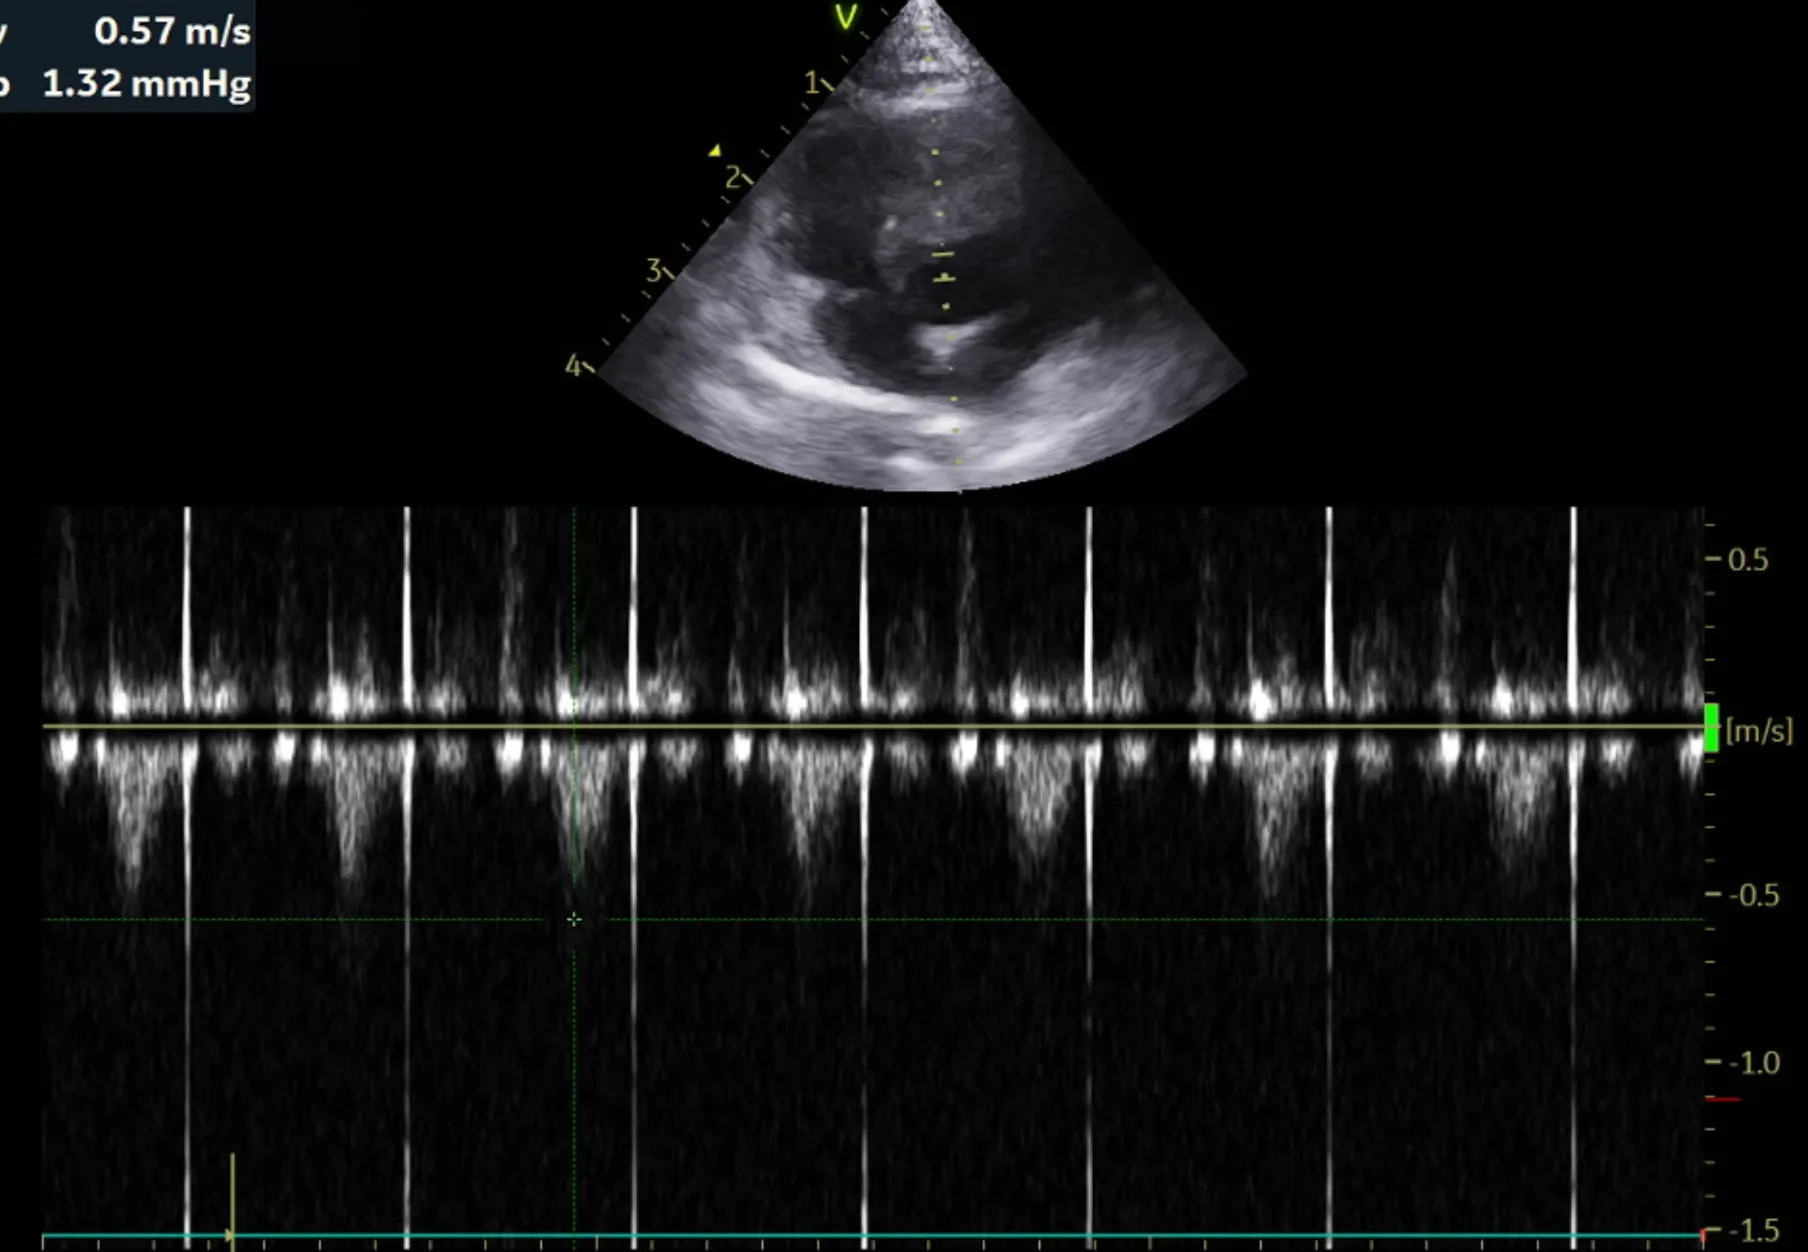

2. 심장 초음파 검사 결과

곰이 의 심장초음파 영상전공의 소견은 다음과 같습니다.

RPS long axis 4 chamber view

LA와 RA내 aliasing pattern 관찰안됨.

LA dilation 관찰안됨.

RPS short axis heart base view

LA/Ao ratio 1.47로 정상범위(0.88-1.7), 유의미한 LA 확장 없음

Left apical 4 chamber view

유의미한 MR flow, TR flow 관찰되지 않음

분류 수치

IVSd 4.66/4.58(2.80 - 4.90㎜) - 정상/정상

LVIDd 15.83/15.17(12.20 - 19.20㎜) - 정상/정상

LVPWd 4.21/4.09(2.80 - 4.80㎜) - 정상/정상

IVSs 6.06/5.17(4.30 - 8.40㎜) - 정상/정상

LVIDs 11.20/10.69(5.50 - 12.60㎜) - 정상/정상

LVPWs 4.66/5.02(4.60 - 8.50㎜) - 정상/정상

EF 59.9%/60.5%(40% - 67%) - 정상/정상

FS 29.3%/29.5%(30% - 49%) - 감소/감소

LVIDDN 0.98

EDVI 23(~100)

ESVI 9(~30)

Echo_comments

HCM으로 의심될만한 소견 관찰되지 않음

주치의 소견은 다음과 같습니다.

곰이 는 심장 초음파 검사 결과 현재 심잠벽의 두께는 정상이며 수축기능, 이완기능(심장이 정상적으로 잘 뛰는 것을 확인하는 검사) 모두 정상입니다.

심장 초음파는 1년에 한번씩 검사 받는 것을 추천드립니다.